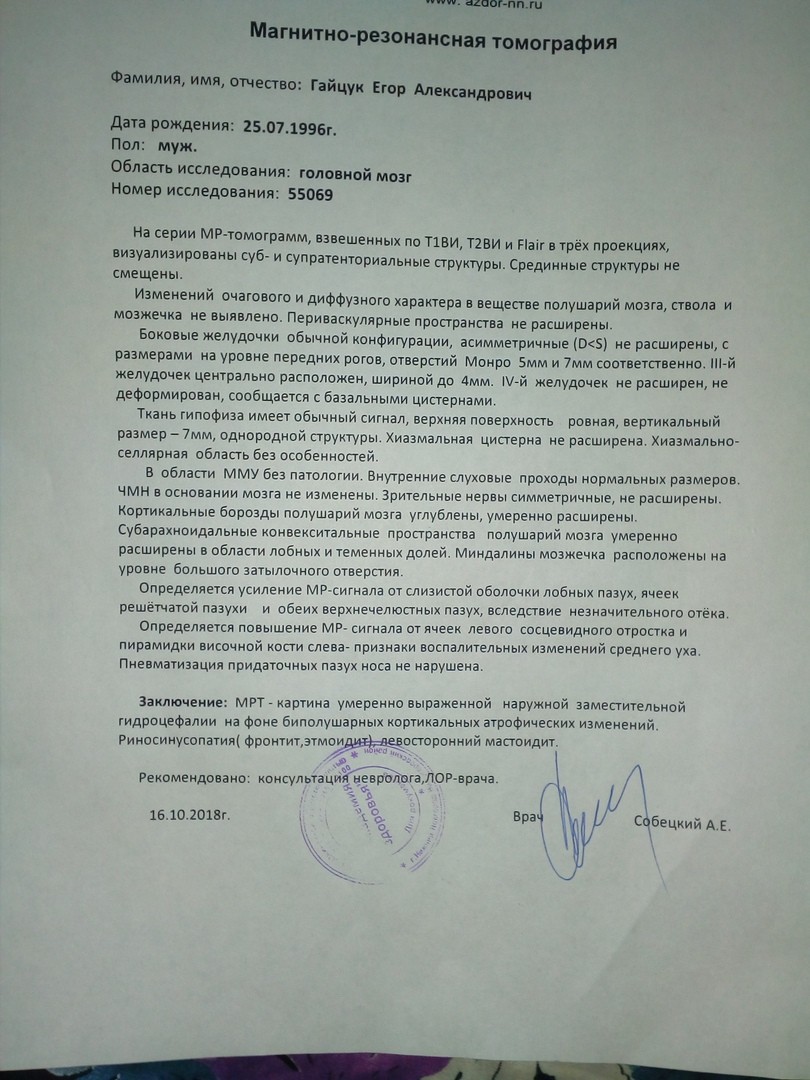

МРТ головного мозга: Расшифровка снимков и Интерпретация

Раздел: Визуальные уроки